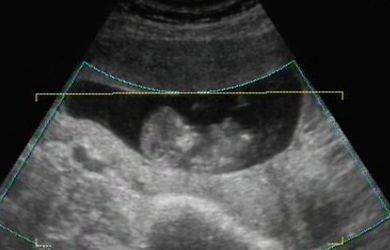

Ma voltam nyaki redő mérésen, integrált teszten. A nyaki redő 0.7 :D

A méretei alapján nem 11 hetes vagyok, hanem kb 1 héttel idősebb.

Rettenetesen ficánkolt, kaptam róla dvd-t is. Boldog vagyok, hogy megörökítettük!!! Hallottam a szive kalapálását és láthattam a kis kezeit, lábait... Velem volt a párom is, gondolhatjátok mennyire boldog volt ő is!

Rakok fel nektek képeket:

Kép Kép Kép Kép